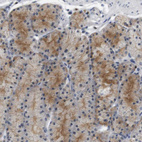

Immunohistochemical staining of human placenta shows strong nuclear positivity in trophoblastic cells.